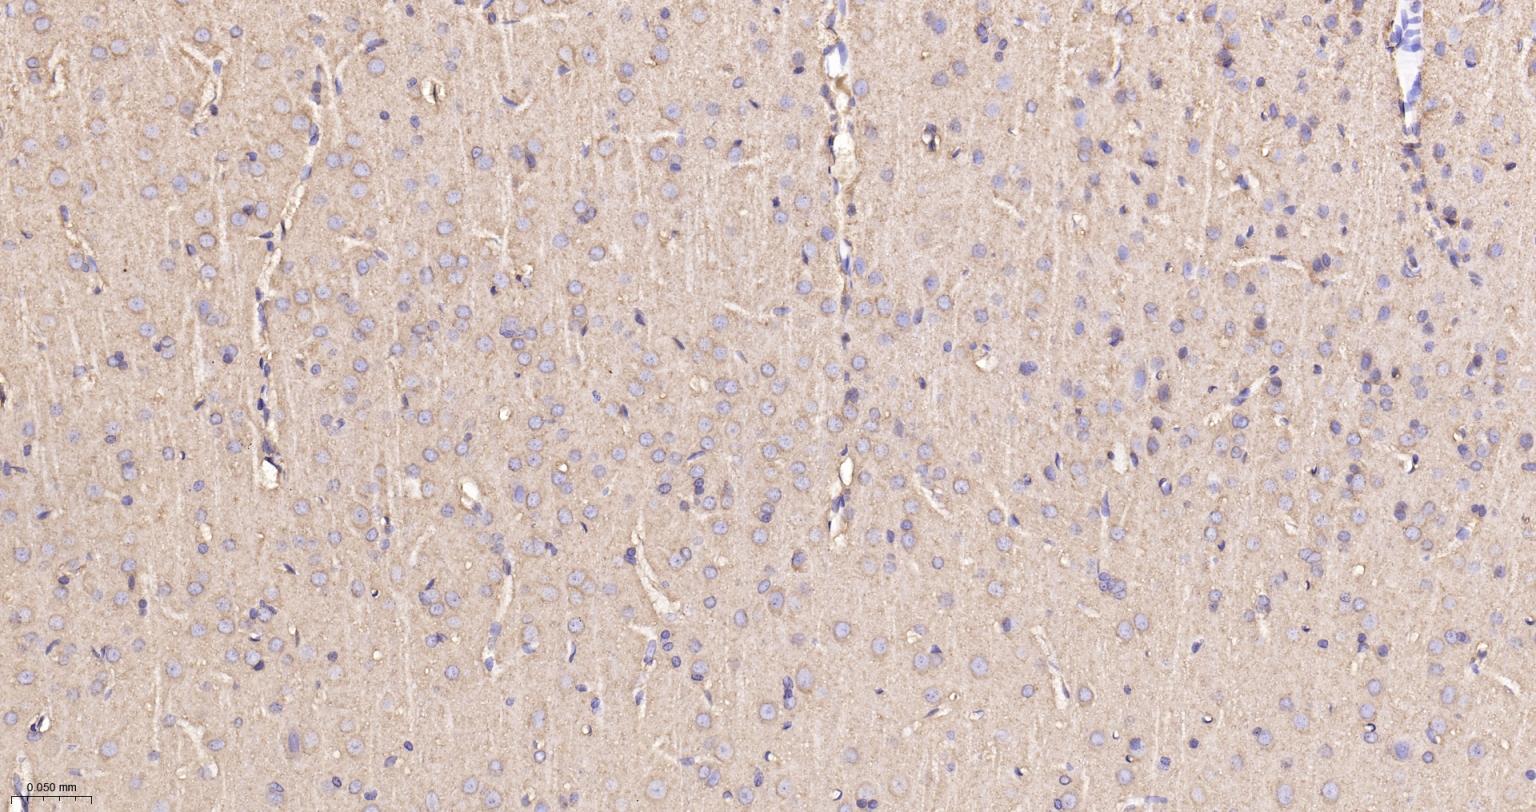

Paraformaldehyde-fixed, paraffin embedded Human Cerebrum; Antigen retrieval by boiling in sodium citrate buffer (pH6.0) for 15 min; The section was incubated with PP2A alpha/beta Monoclonal Antibody, Unconjugated (bsm-61223R) at 1:200 overnight at 4°C, followed by conjugation to the bs-0295G-HRP and DAB (C-0010) staining.

Paraformaldehyde-fixed, paraffin embedded Rat Cerebrum; Antigen retrieval by boiling in sodium citrate buffer (pH6.0) for 15 min; The section was incubated with PP2A alpha/beta Monoclonal Antibody, Unconjugated (bsm-61223R) at 1:200 overnight at 4°C, followed by conjugation to the bs-0295G-HRP and DAB (C-0010) staining.

Paraformaldehyde-fixed, paraffin embedded Mouse Cerebrum; Antigen retrieval by boiling in sodium citrate buffer (pH6.0) for 15 min; The section was incubated with PP2A alpha/beta Monoclonal Antibody, Unconjugated (bsm-61223R) at 1:200 overnight at 4°C, followed by conjugation to the bs-0295G-HRP and DAB (C-0010) staining.